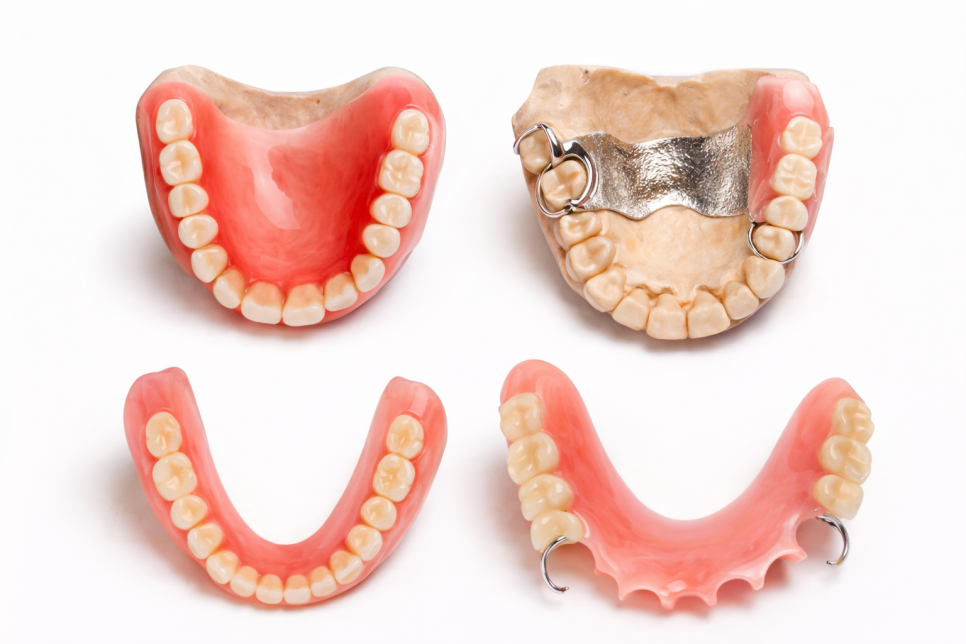

틀니는 크게 총의치와 부분의치로

나눌 수 있습니다.

총의치는 한 악궁의 모든 치아가 상실된 경우

전체를 덮는 형태의 틀니입니다.

위턱 전체 또는 아래턱 전체를

하나의 틀니로 수복하게 됩니다.

부분의치는 일부 치아만 상실된 경우

남아 있는 자연치아에 고리를 걸어

유지력을 얻는 형태의 틀니입니다.

이 외에도 임플란트를 활용한 틀니,

특수한 유지 장치를 사용하는 틀니 등

다양한 종류가 존재합니다.